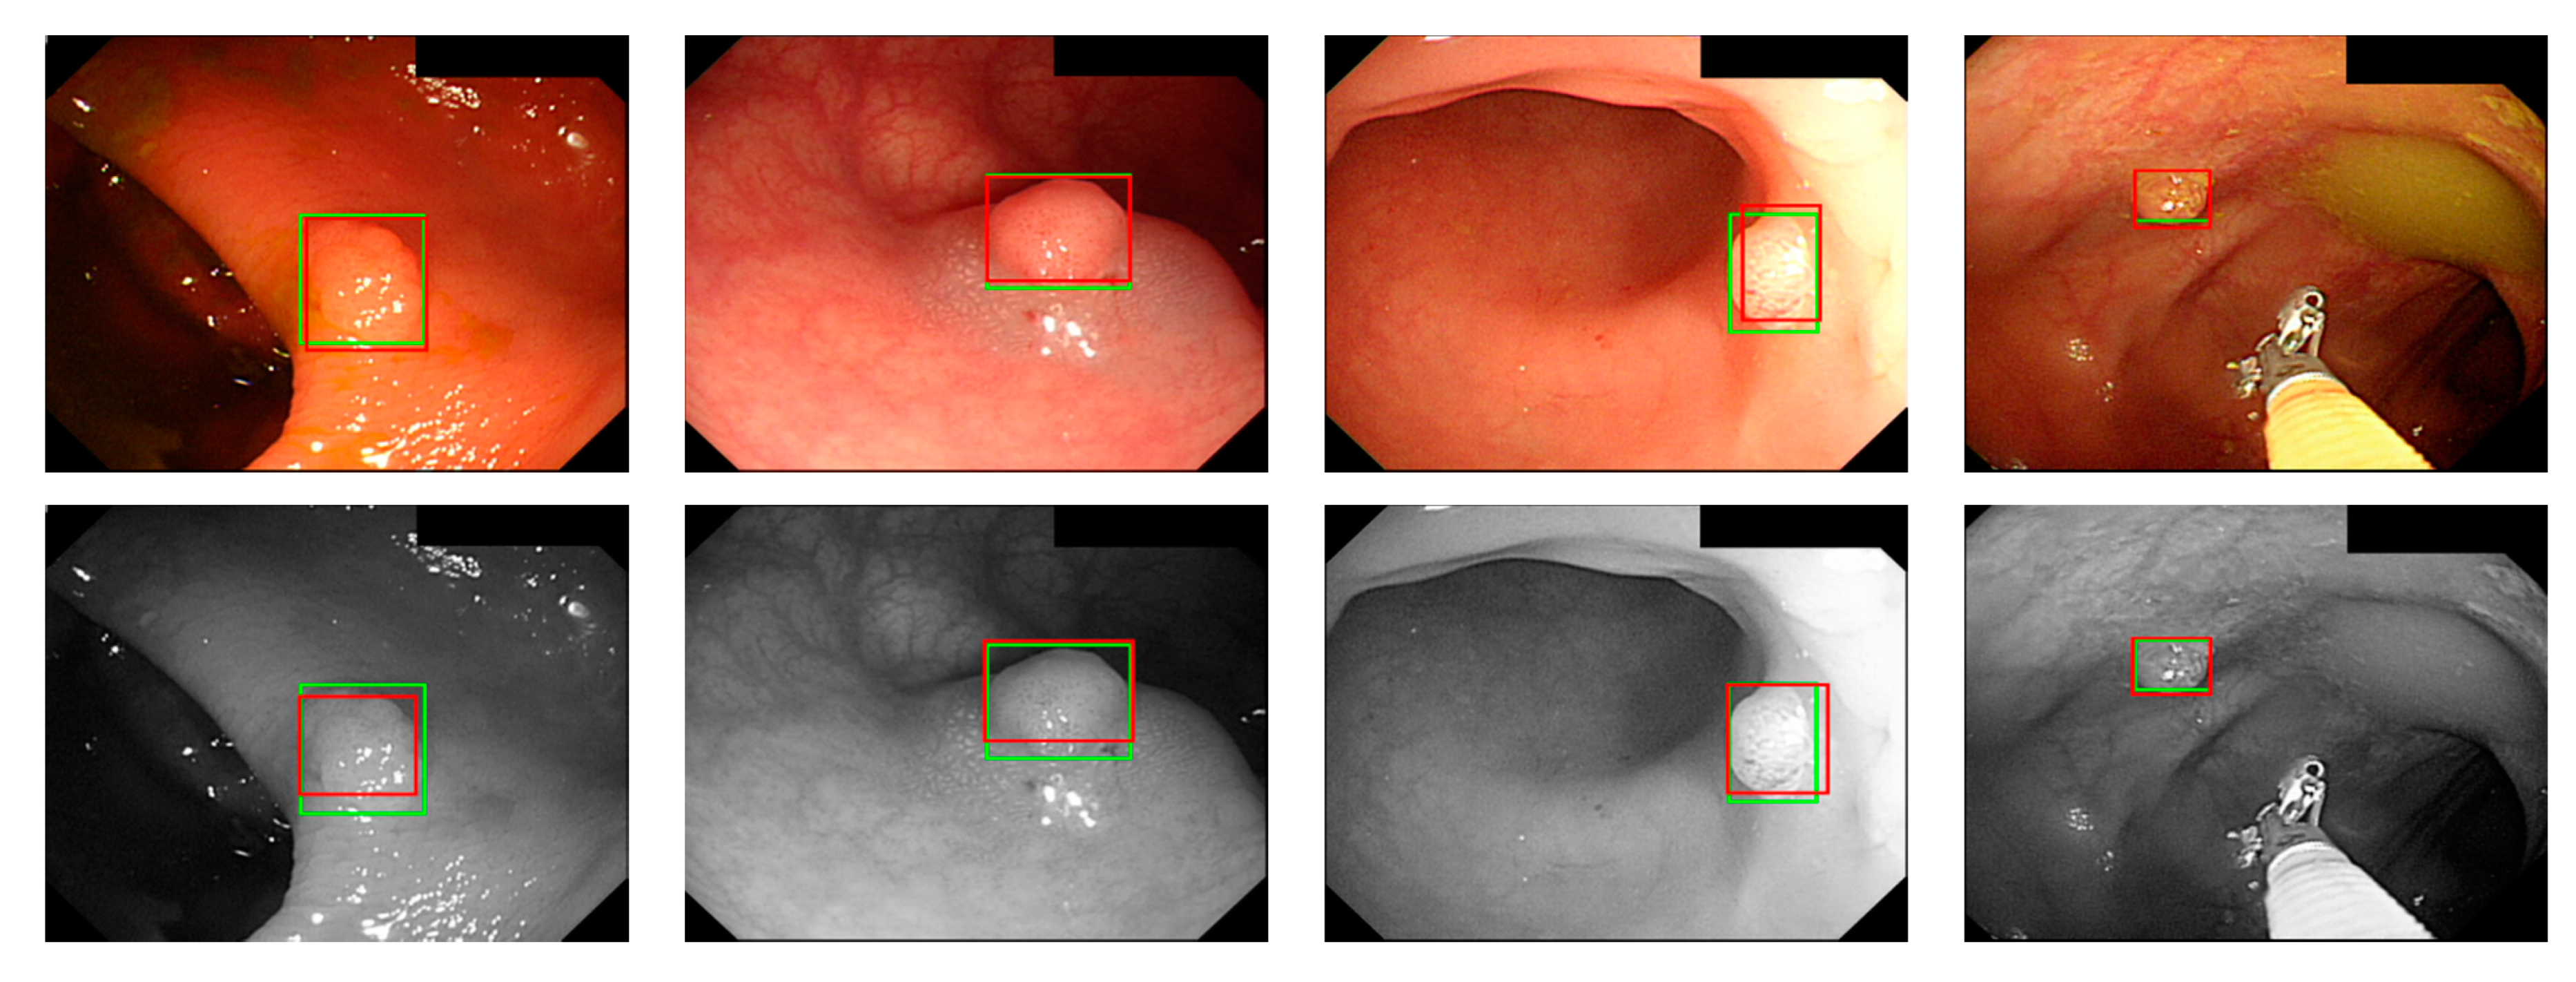

where ai is the input value; p is the pooling regions; n is the pooling size; and aj is the output value after the maximum value is obtained. Polyp detection was then conducted in the bounding box transform layer. The prediction result of the feature map was obtained in the last layer and was output through a 1 × 1 convolutional layer by using a pixel-based approach and converted to a bounding box mode for display [50]. There are eight groups of bounding boxes to locate the polyps: (16, 16), (32, 32), (24, 48), (48, 24), (60, 80), (108, 72), (216, 144), and (180, 180). The cutoff value of polyp detection is 0.2. The size of the predicted bounding box was adjusted by converting it to the range of a true-value bounding box. Table 3 displays the framework of the CNN model. Figure 10 and Figure 11 show the results of WL and NBI polyp detection, respectively, where the first column is the RGB image; the second column is the grayscale image; the red box is the prediction box; and the green box is the actual polyp location marked by the clinician, namely the GT.

Figure 10. WL polyp detection.

Sensors 21 05995 g010

Figure 11. NBI polyp detection.